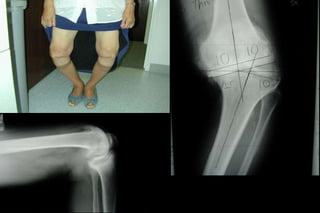

Workup

• Plain xrays

– Knee

»STANDING AP!!!!!

»Lateral

»Merchant/Sunrise

»Consider Rosenberg view

Weight-Bearing Xrays